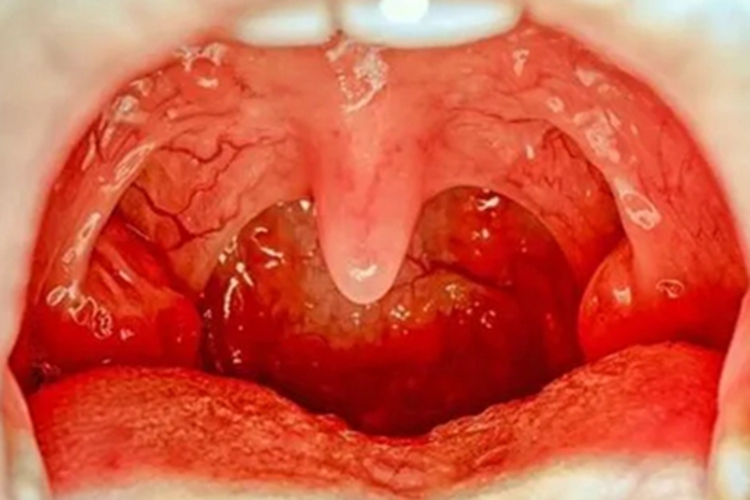

淋菌性咽炎患者在临床上可表现为咽后壁出现明显红肿,两侧扁桃体也发生肿大,张口能看到蚕豆大小的鲜红色扁桃体,表面没有明确的炎性分泌物,但是能够看到充血的血丝。